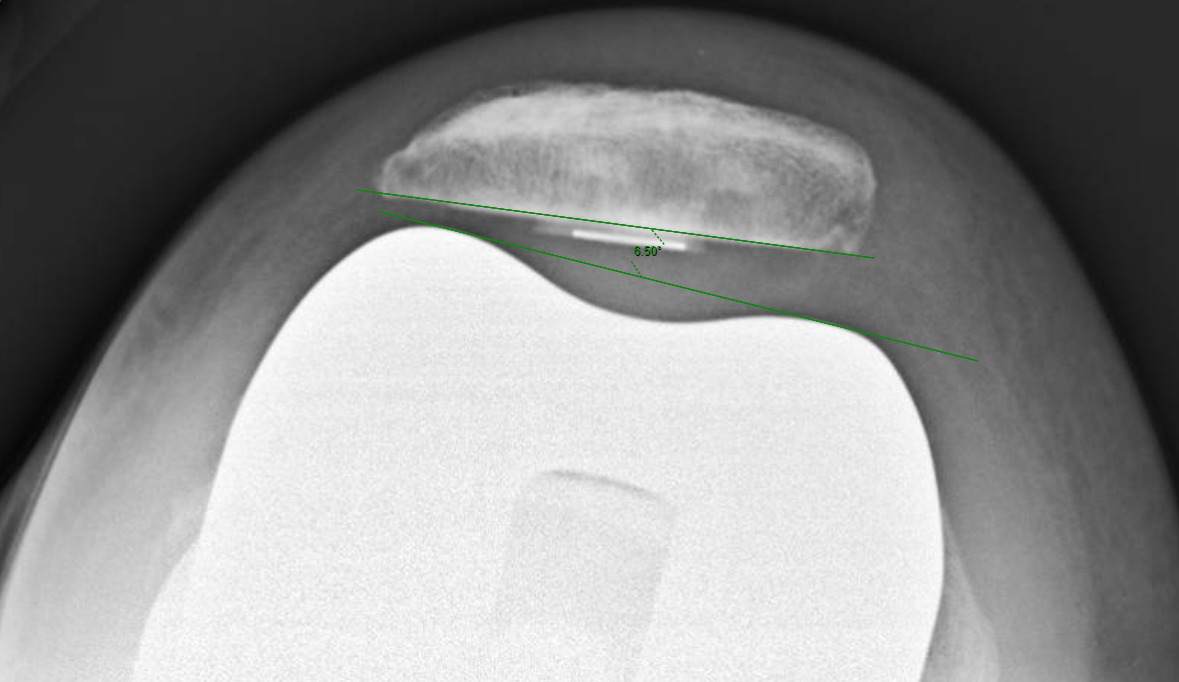

Measurements were performed by one rater following extensive training from the senior author using a standardized measurement protocol. The rater was blinded to the use of robotics when measurements were made. Assessment of postoperative merchant view radiographs on digital imaging software according to the method of Gomes et al. was conducted (Gomes, Bechtold, and Gustilo 1988). The angle between the resected surface of the patella and a line tangent to the anterior condylar axis of the femoral component was measured and recorded (Figures 1-4). The patellar tilt was recorded as positive when the tilt was lateral and was recorded as negative when the tilt was medial. The absolute value of the patellar tilt was used during data analysis as a neutral of 0° was considered the goal for patellar tilt during surgery, and both increasing lateral and medial tilt away from neutral were considered as increasingly imperfect. The percentage of outliers where the patellar tilt exceeded 3 degrees off neutral was also calculated for each group.